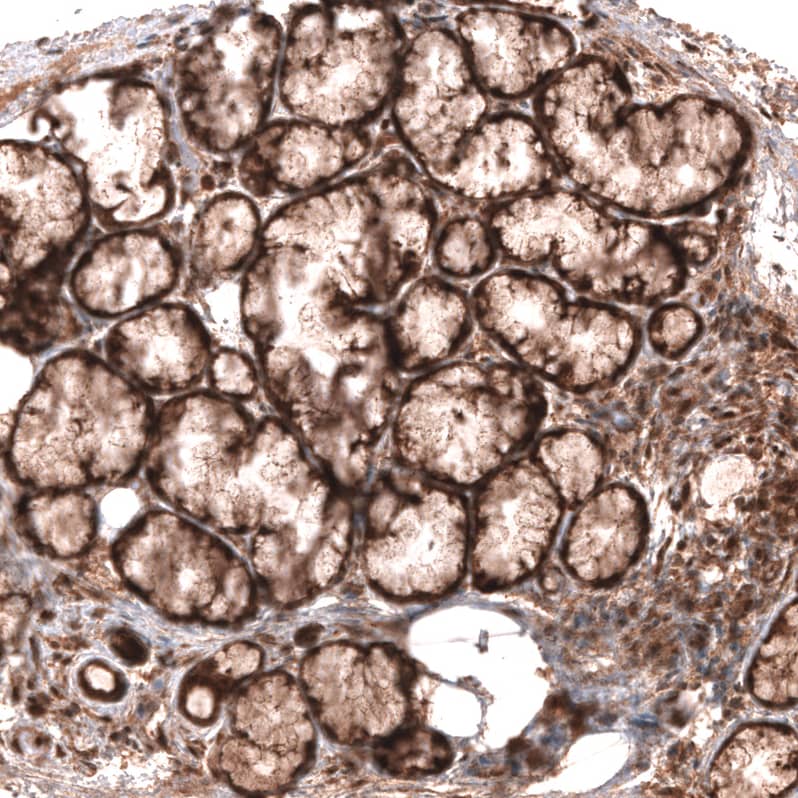

Staining of human placenta shows strong cytoplasmic positivity in trophoblastic cells.